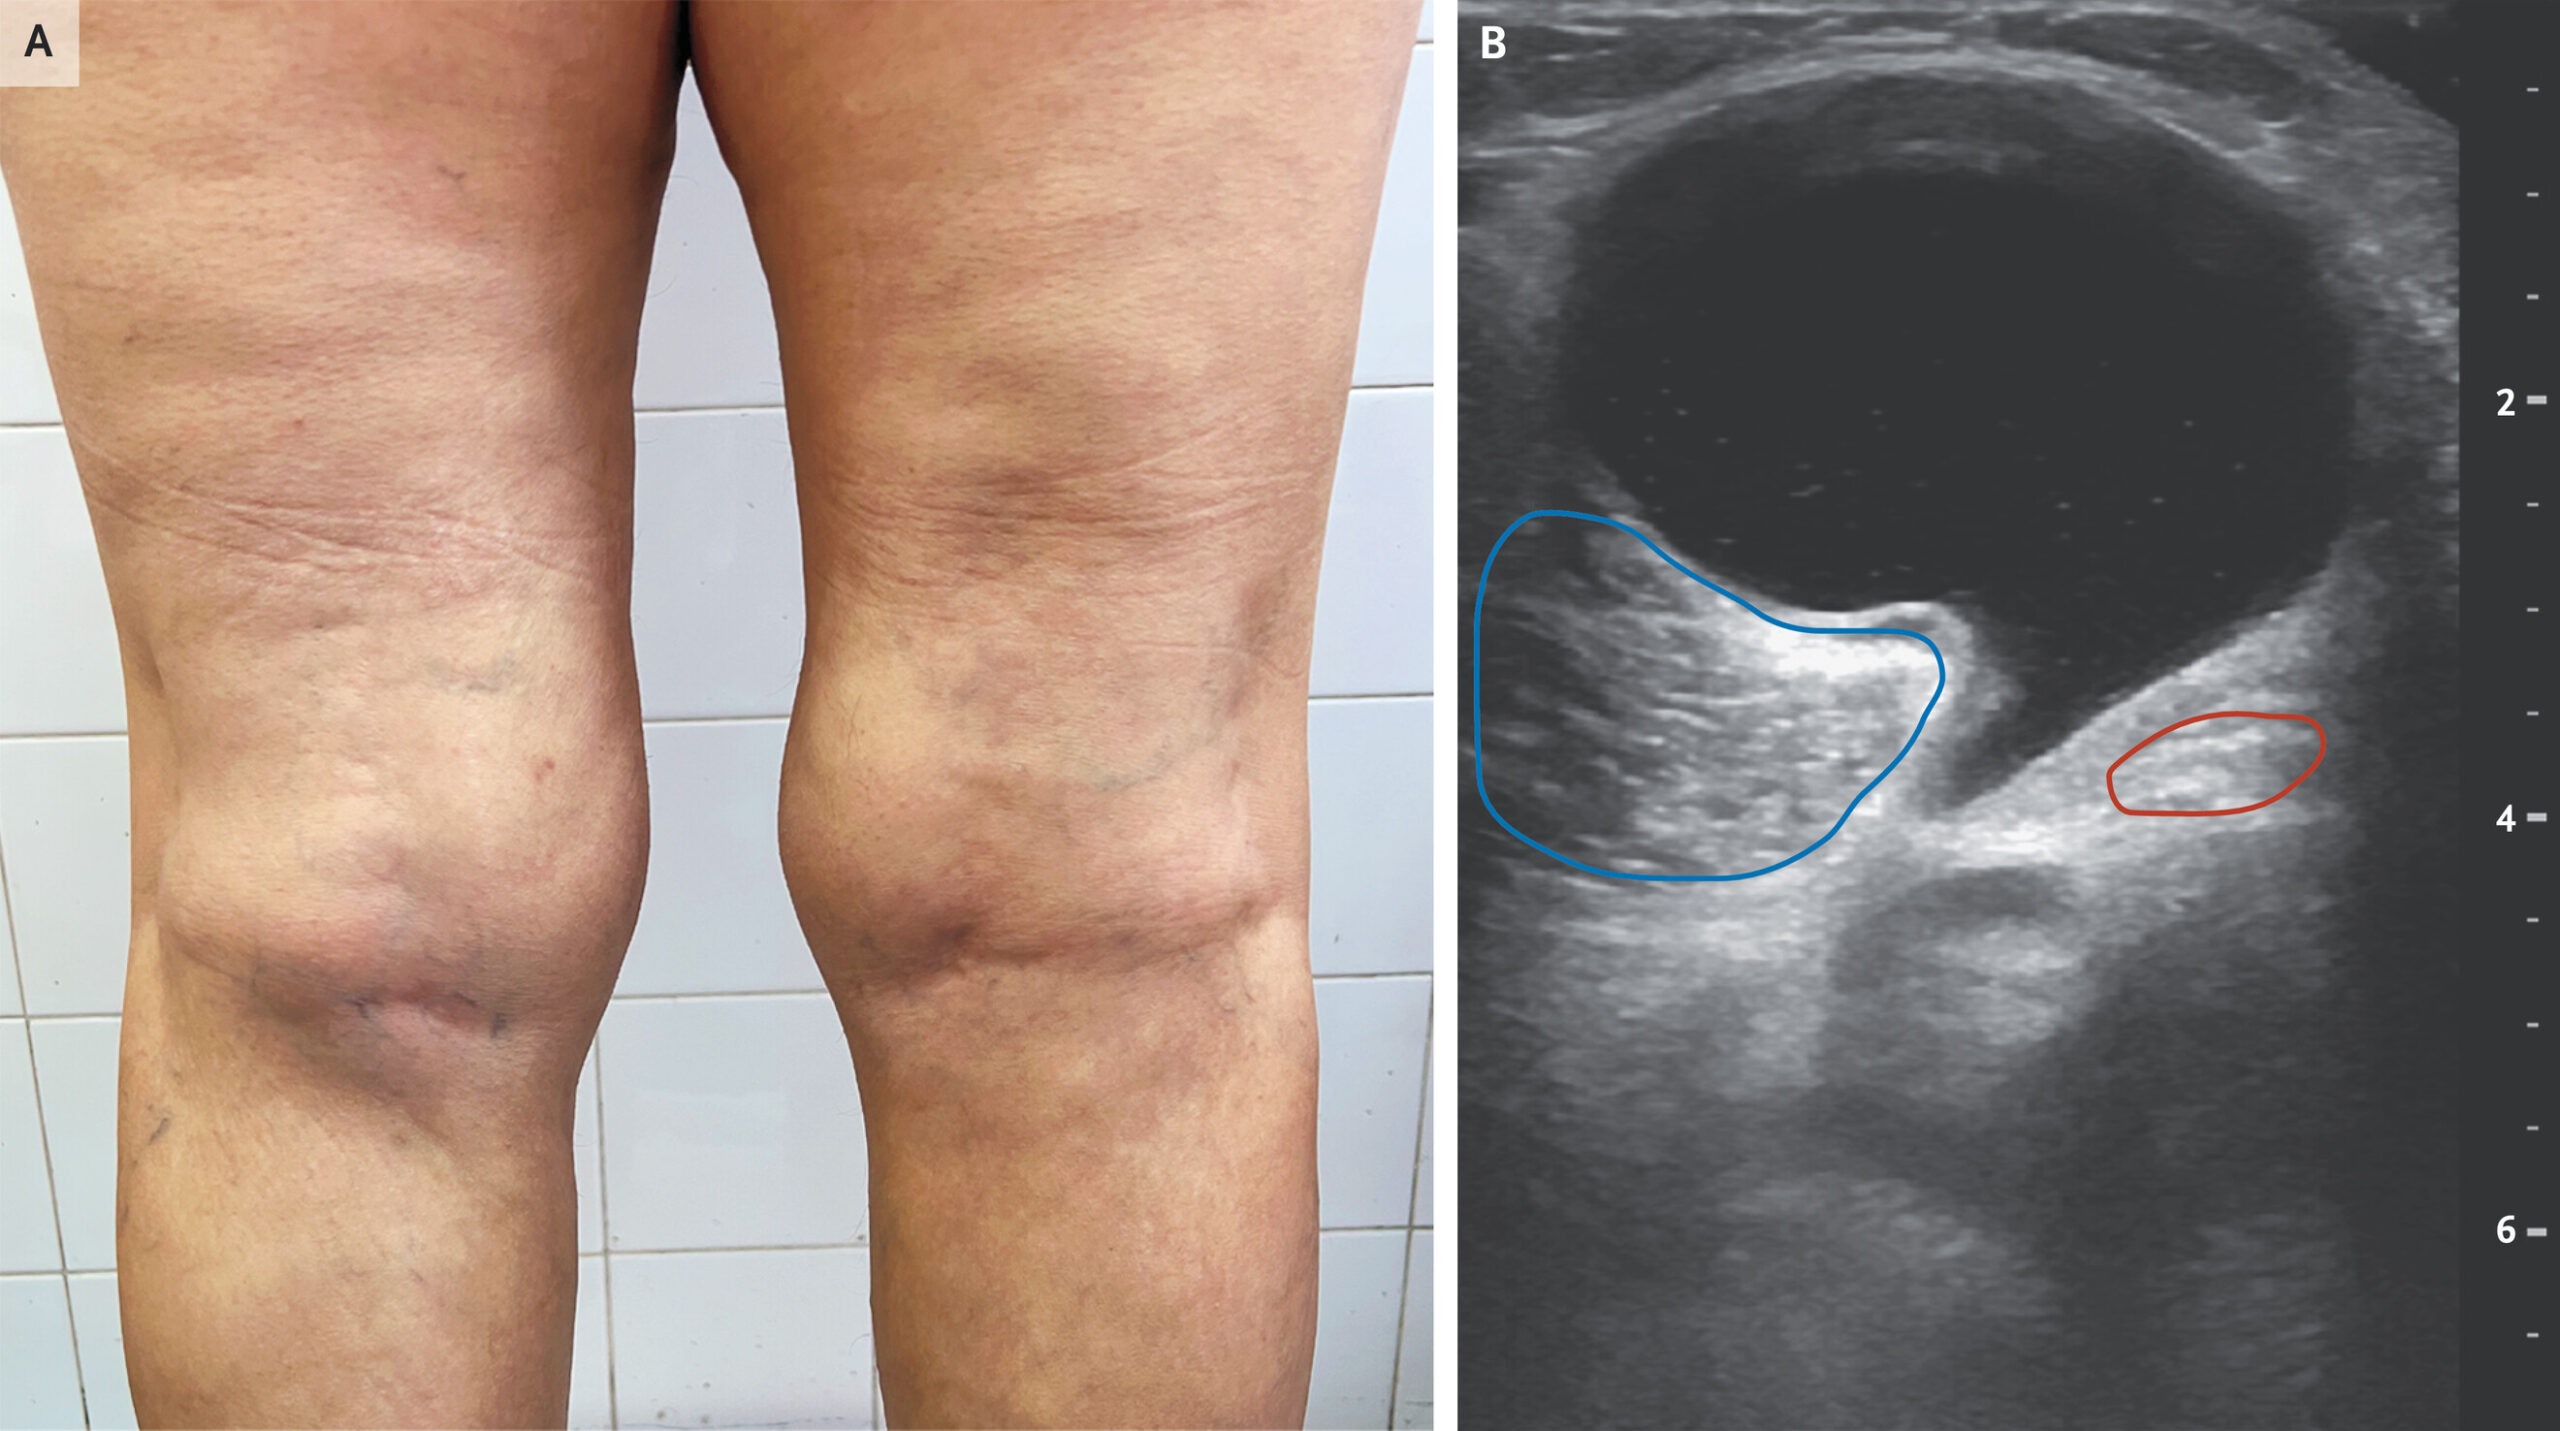

O exame físico pode mostrar abaulamento na região poplítea, desconforto posterior, derrame articular e limitação da mobilidade. O contexto clínico ajuda bastante, mas o diagnóstico definitivo geralmente depende de imagem.

Ultrassonografia

A ultrassonografia é um exame muito útil para confirmar o cisto e avaliar seu conteúdo. Em casos de ruptura, pode demonstrar líquido dissecando os planos da perna. Também é importante para ajudar a afastar trombose venosa profunda.